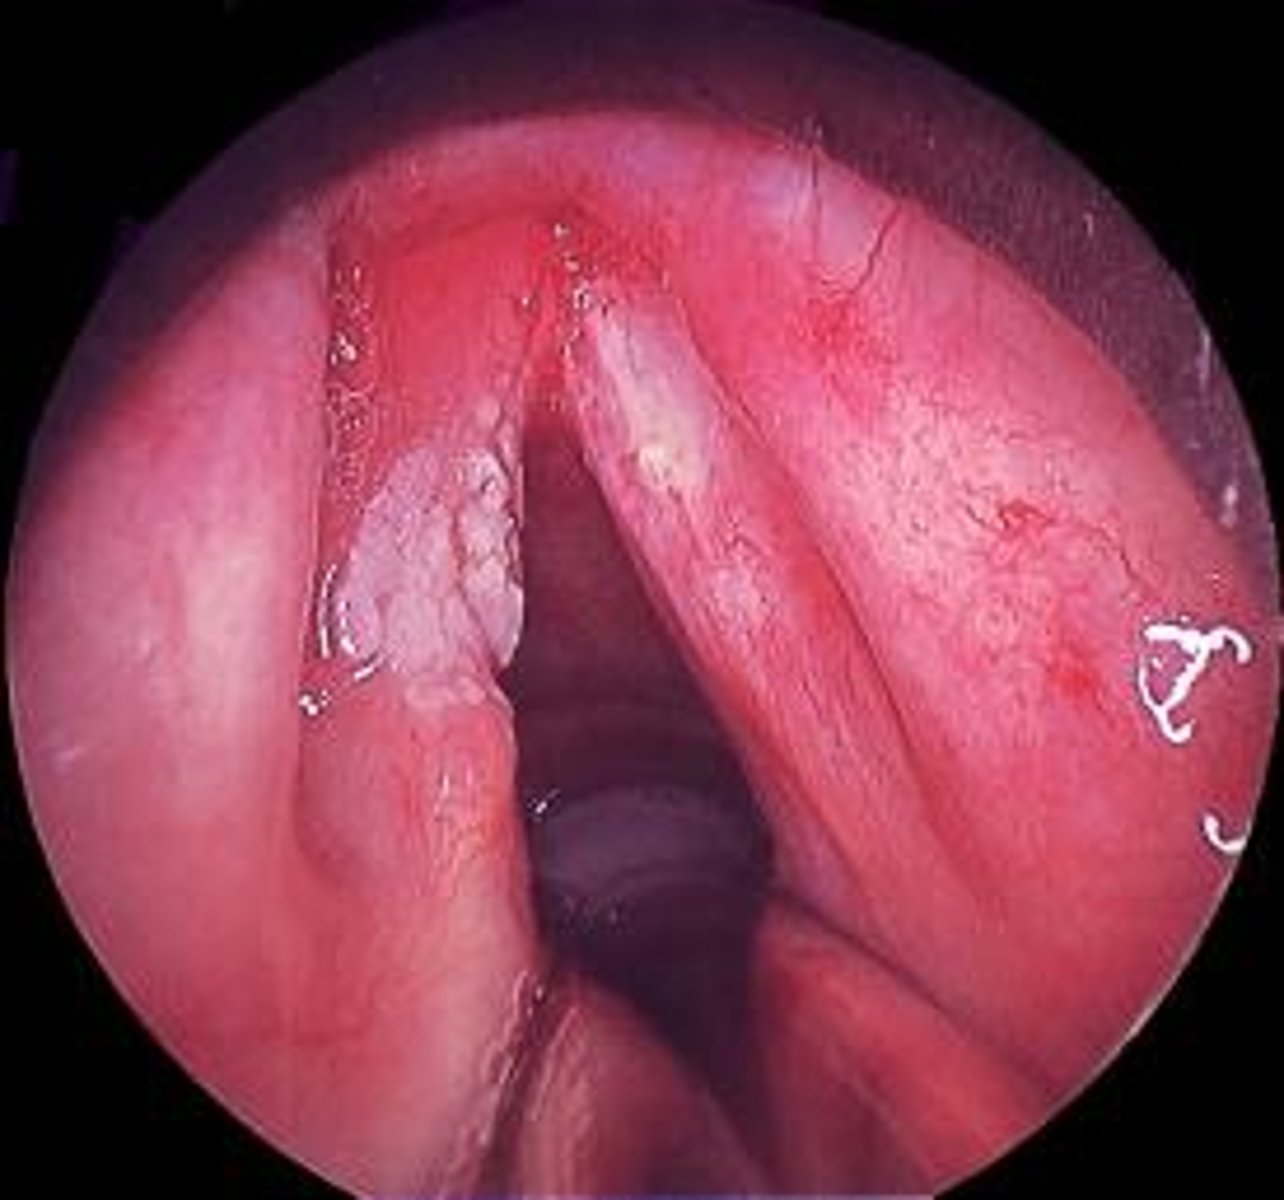

What are vocal nodules?

Localized growths on the vocal folds, often bilateral and common in professional voice users.

What is a common treatment for newly formed vocal nodules?

What are vocal polyps?

Fluid-filled lesions on the vocal folds, larger than nodules and can be unilateral or bilateral.